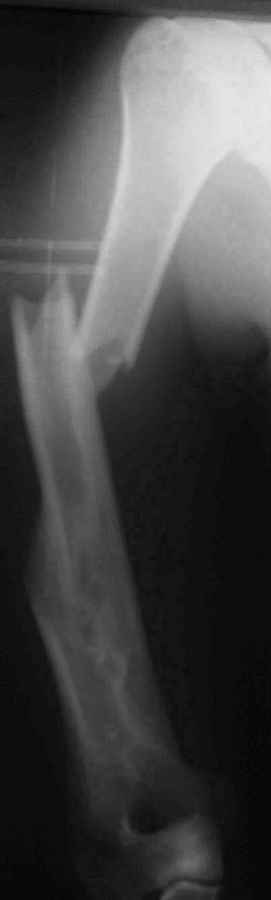

Результат консервативного лечения короткого косого перелома диафиза плеча врачами общей практики в условиях развивающейся страны у больного low social class

Предыдущий перелом плеча – пару лет назад ДТП. К сожалению, этот крайне важный жизненный опыт не изменил стиль вождения больного Последний перелом плеча – ДТП 2 мес назад. В связи с дефицитом как специалистов – ортопедов, так и операционного времени в принципе больной был осмотрен в приемном покое врачом общей практики, наложена U-образная гипсовая повязка и отправлен домой. Я впервые увидел больного через 6 нед после травмы, сделал снимки и снял повязку. Фотографии больного - 2 мес после травмы. снимки - при травме и через 6 недель

Вывод: Если плечо не трогать, оно нормально срастается.

Тот же самый вывод наукообразно: данное клиническое наблюдение свидетельствует, что консервативное лечение переломов диафиза плеча является патофизиологически оптимальным, приводит к удовлетворительному функциональному результату и явлеяется наиболее экономически щадящим как для больного, так и для системы государственного здравоохранения в целом.